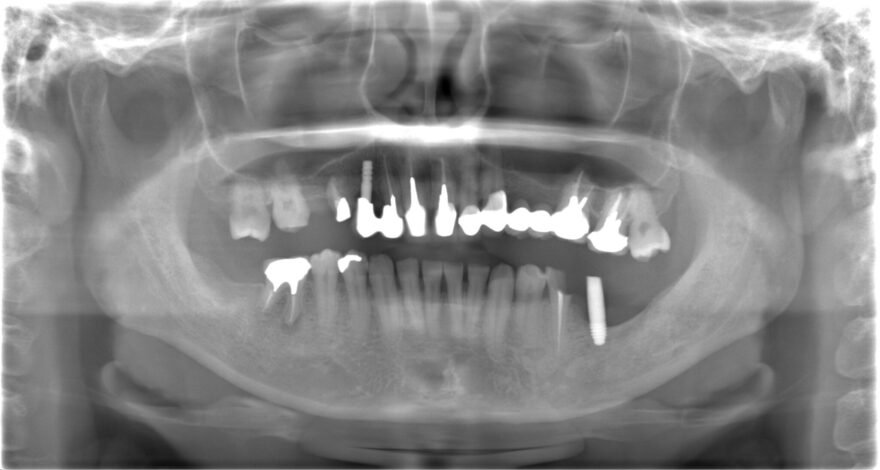

Before

全体的な噛み合わせが狂ってしまい、どこで噛んでいいか分からない状態でした。

8本のインプラント治療と16本のセラミック治療で、しっかり上下の歯が噛み合う状態にしました。

奥歯インプラント8本→3,520,000円(税込)

《1本あたり440,000円(税込)》

前歯プレミアムセラミック12本→1,980,000円

《1本あたり165,000円(税込)》

奥歯プレミアムセラミック10本→1,430,000円

《1本あたり143,000円(税込)》

ファイバーコア5本→110,000円(税込)

《1本あたり22,000円(税込)》

前歯精密根管治療2本→220,000円

《1本あたり110,000円(税込)》

咬合再構成(全ての仮歯代とデジタルデザイン含む)24本→792,000円

《1本あたり33,000円(税込)》

総額 8,052,000円(税込)